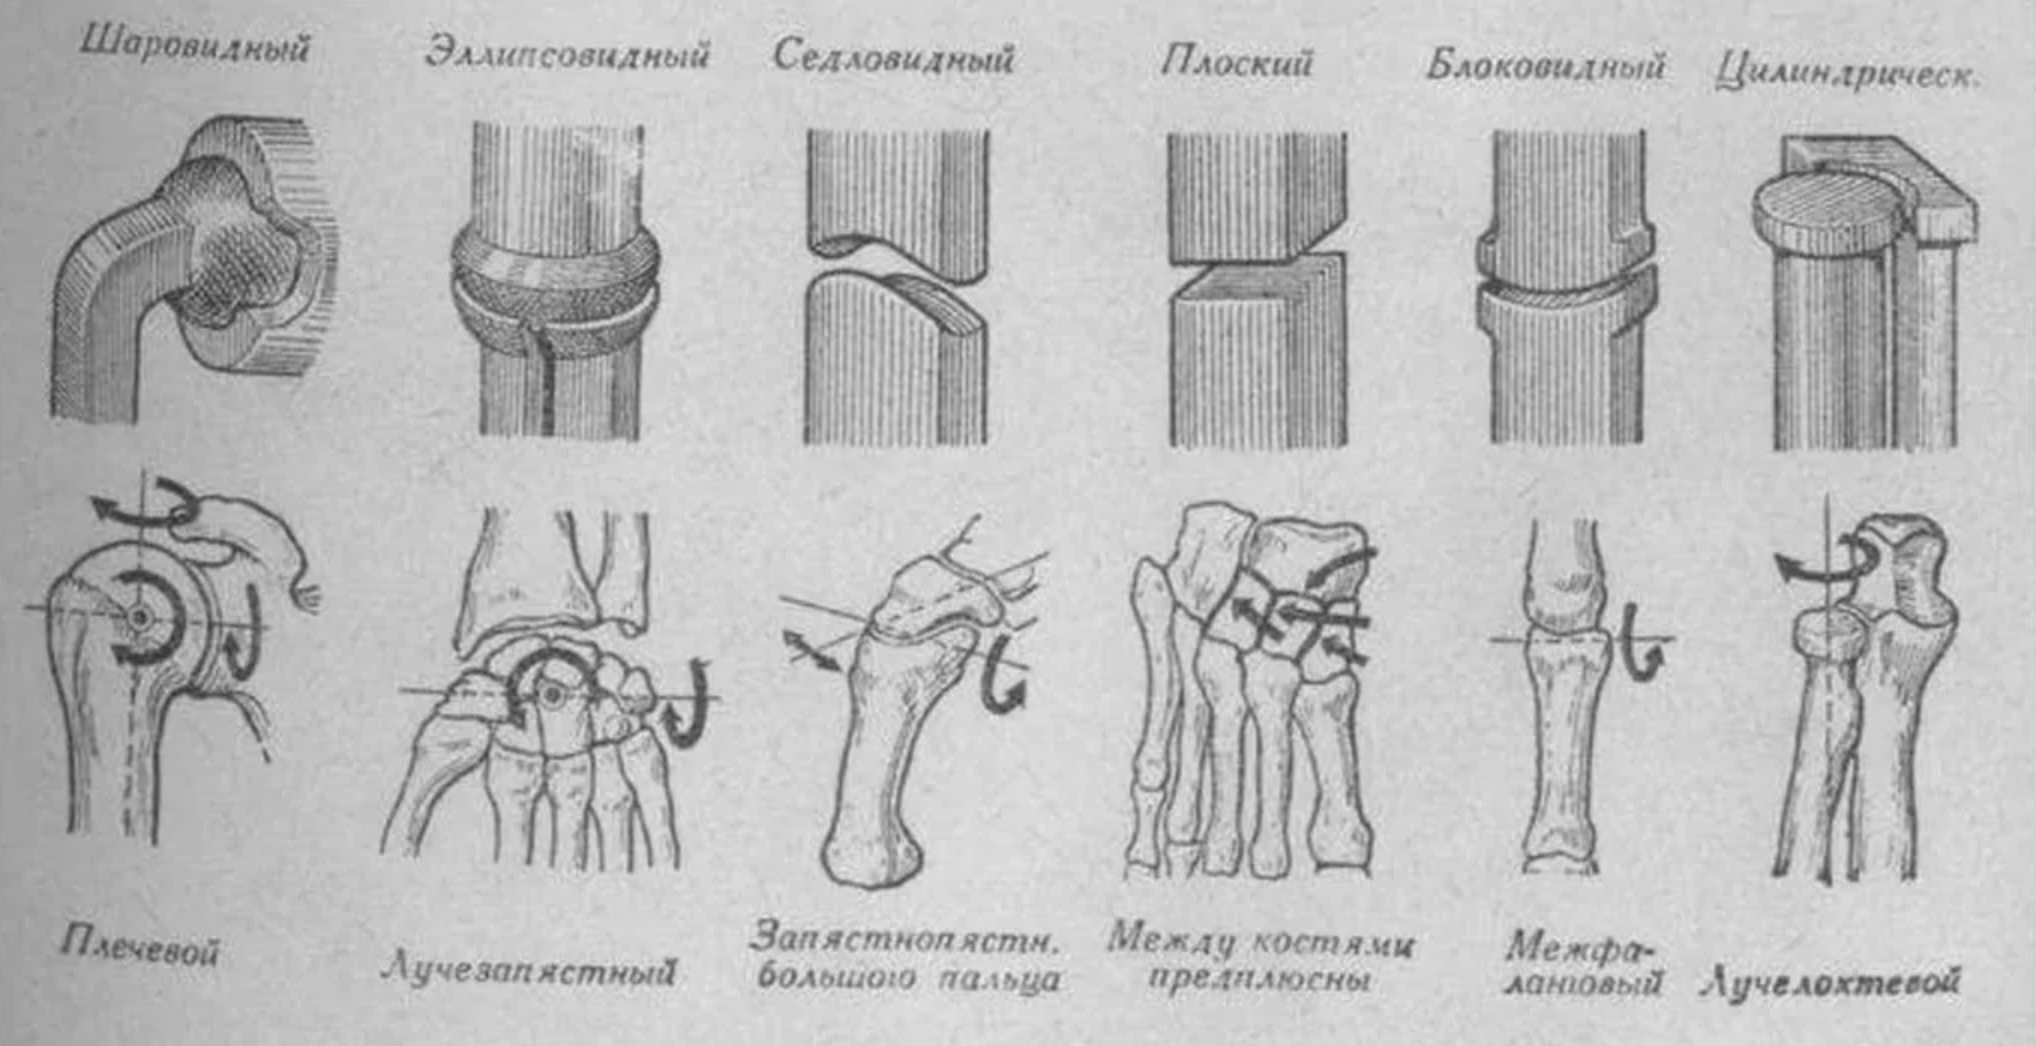

Структура и анатомия синдесмоза: научные иллюстрации